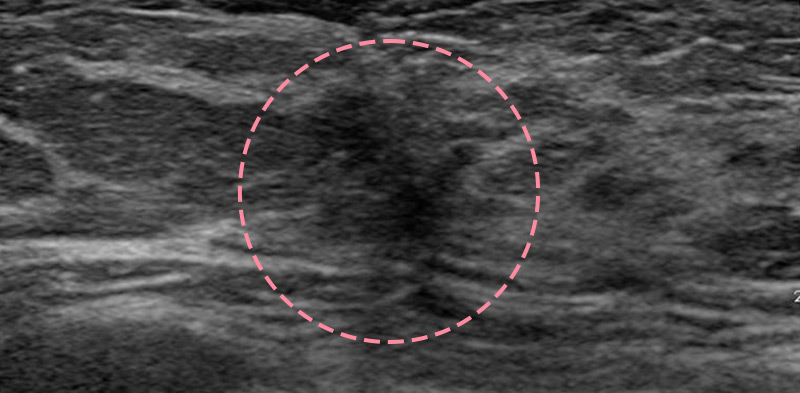

매우 빠르게 자라는 유방 종양 수술을 위해 외국에서 내원한 17세 환자의 사례입니다.

3cm 이상의 유방 종양은 외과적 수술로 제거하는 것이 원칙이고, 대부분의 경우 대학병원으로 연계됩니다.

그러나 한송이 원장은 대학병원에서의 고난도 시술 경력을 다수 보유하고 있어 크기가 큰 종양도 맘모톰 시술로 가능하였습니다.

3번에 걸쳐 맘모톰시술을 시행한 결과 성공적으로 제거를 마칠 수 있었습니다. 외과적 절제로 생길 수 있었을 흉터를 원치 않으셨던 환자와 보호자분 모두 시술 결과에 만족하셨습니다. 매년 추적 검사를 시행하고 있으며, 깨끗이 제거된 상태를 잘 유지하는 중입니다.